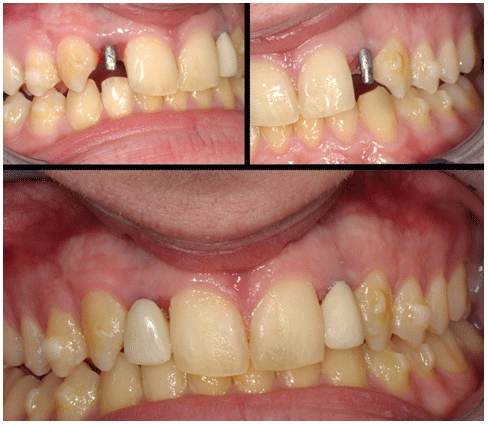

Figure 1: The case of the young male patient suffering from bilateral agenesis. The lack of space between central incisors and canine can be observed.

This report is about a 13.y.o. male patient, Caucasian, suffering from agenesis of both lateral incisors in bilateral class one molar (2.1 1.2) in good health status. He showed a deep bite, resulting in a remarkable reduction of transverse diameters in the central group.

The above pictures prove, therefore, how the orthodontic Invisalign® treatment ensured to achieve more space. In this very case, the therapy lasted from May 2011 until April 2014, using overall 90 aligners gaining a total of 4,9 mm as space for the 1.2 and 4.8 mm for the 2.2.

The edentulous condition is characterized by little available space, in addition to remarkable bone atrophy. In order to restore the missing tooth, the procedure, previously described, was performed by employing, eventually, noble-metal alloy, and ceramic (Ivoclar Vivadent InLine®) crowns (Figures 1-8).

Figure 2: The space gained after the orthodontic treatment in order to insert conservatively the implants.